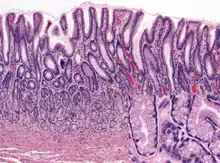

Microanatomy

Wall

Like the other parts of the gastrointestinal tract, the human stomach walls consist of a mucosa, submucosa, muscularis externa, subserosa and serosa.[16]

The inner part of the lining of the stomach, the gastric mucosa, consists of an outer layer of column-shaped cells, a lamina propria, and a thin layer of smooth muscle called the muscularis mucosa. Beneath the mucosa lies the submucosa, consisting of fibrous connective tissue.[17] Meissner's plexus is in this layer interior to the oblique muscle layer.[18]

Glands

The mucosa lining the stomach is lined with gastric pits, which receive gastric juice, secreted by between 2 and 7 gastric glands. Gastric juice is an acidic fluid containing hydrochloric acid and the digestive enzyme pepsin. The glands contains a number of cells, with the function of the glands changing depending on their position within the stomach.

Within the body and fundus of the stomach lie the fundic glands. In general, these glands are lined by column-shaped cells that secrete a protective layer of mucus and bicarbonate. Additional cells present include parietal cells that secrete hydrochloric acid and intrinsic factor, chief cells that secrete pepsinogen (this is a precursor to pepsin- the highly acidic environment converts the pepsinogen to pepsin), and neuroendocrine cells that secrete serotonin.[22]

Glands differ where the stomach meets the esophagus and near the pylorus.[23] Near the gastroesophageal junction lie cardiac glands, which primarily secrete mucus.[22] They are fewer in number than the other gastric glands and are more shallowly positioned in the mucosa. There are two kinds - either simple tubular glands with short ducts or compound racemose resembling the duodenal Brunner's glands. Near the pylorus lie pyloric glands located in the antrum of the pylorus. They secrete mucus, as well as gastrin produced by their G cells.[24]